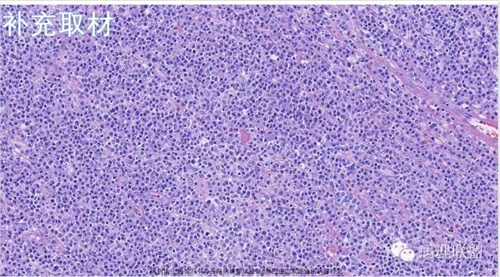

M,79岁,右半结肠粘膜下肿块。大小:6.5*6*6cm球形肿块,切面灰白质硬,界清。第一次取材。